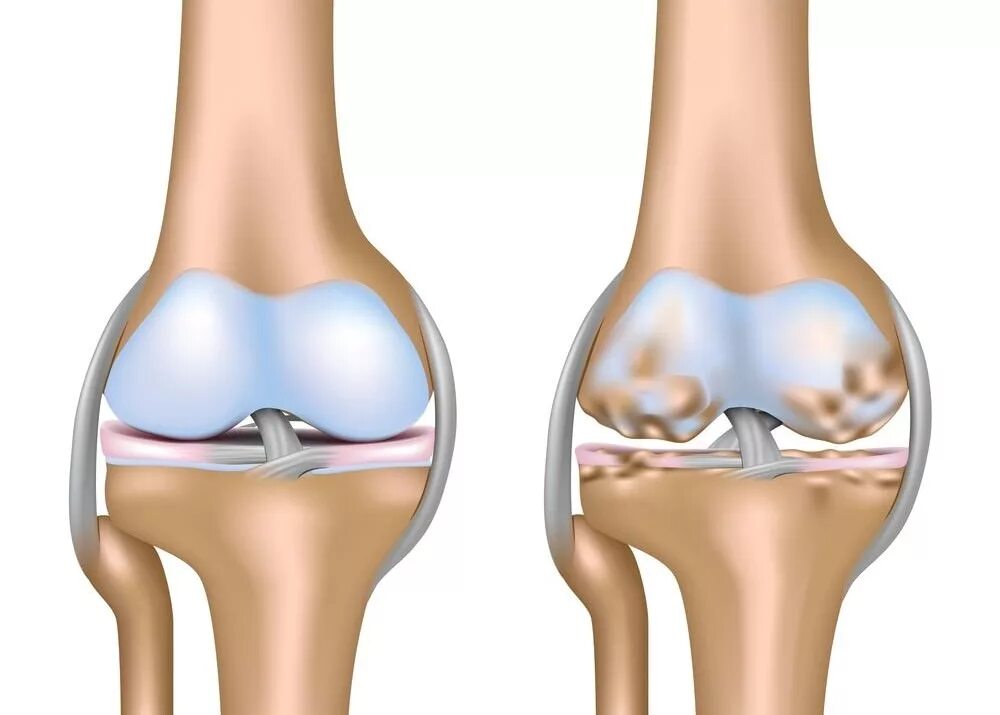

Явления остеоартроза